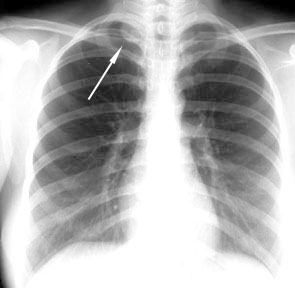

Lordotic View

Lordotic and kyphotic views are helpful whenever a lesion is detected behind the clavicle. The clavicle projects up in the lordotic view and projects down in the kyphotic view, making the lesion visible without the overlapping clavicle.

Lordotic view below.